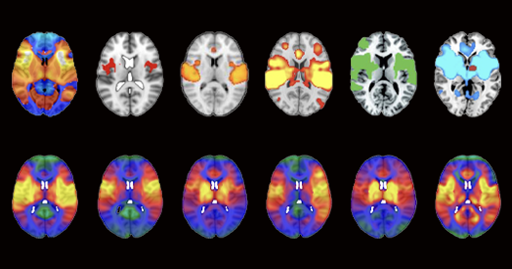

Aleyan@lemmy.world to science@lemmy.worldEnglish · 1 day agoMore than 200 published studies and at least 7 ongoing clinical trials rely on potentially faulty brain network maps, according to a study published in Nature Neurosciencewww.thetransmitter.orgexternal-linkmessage-square0fedilinkarrow-up127arrow-down11file-text

arrow-up126arrow-down1external-linkMore than 200 published studies and at least 7 ongoing clinical trials rely on potentially faulty brain network maps, according to a study published in Nature Neurosciencewww.thetransmitter.orgAleyan@lemmy.world to science@lemmy.worldEnglish · 1 day agomessage-square0fedilinkfile-text